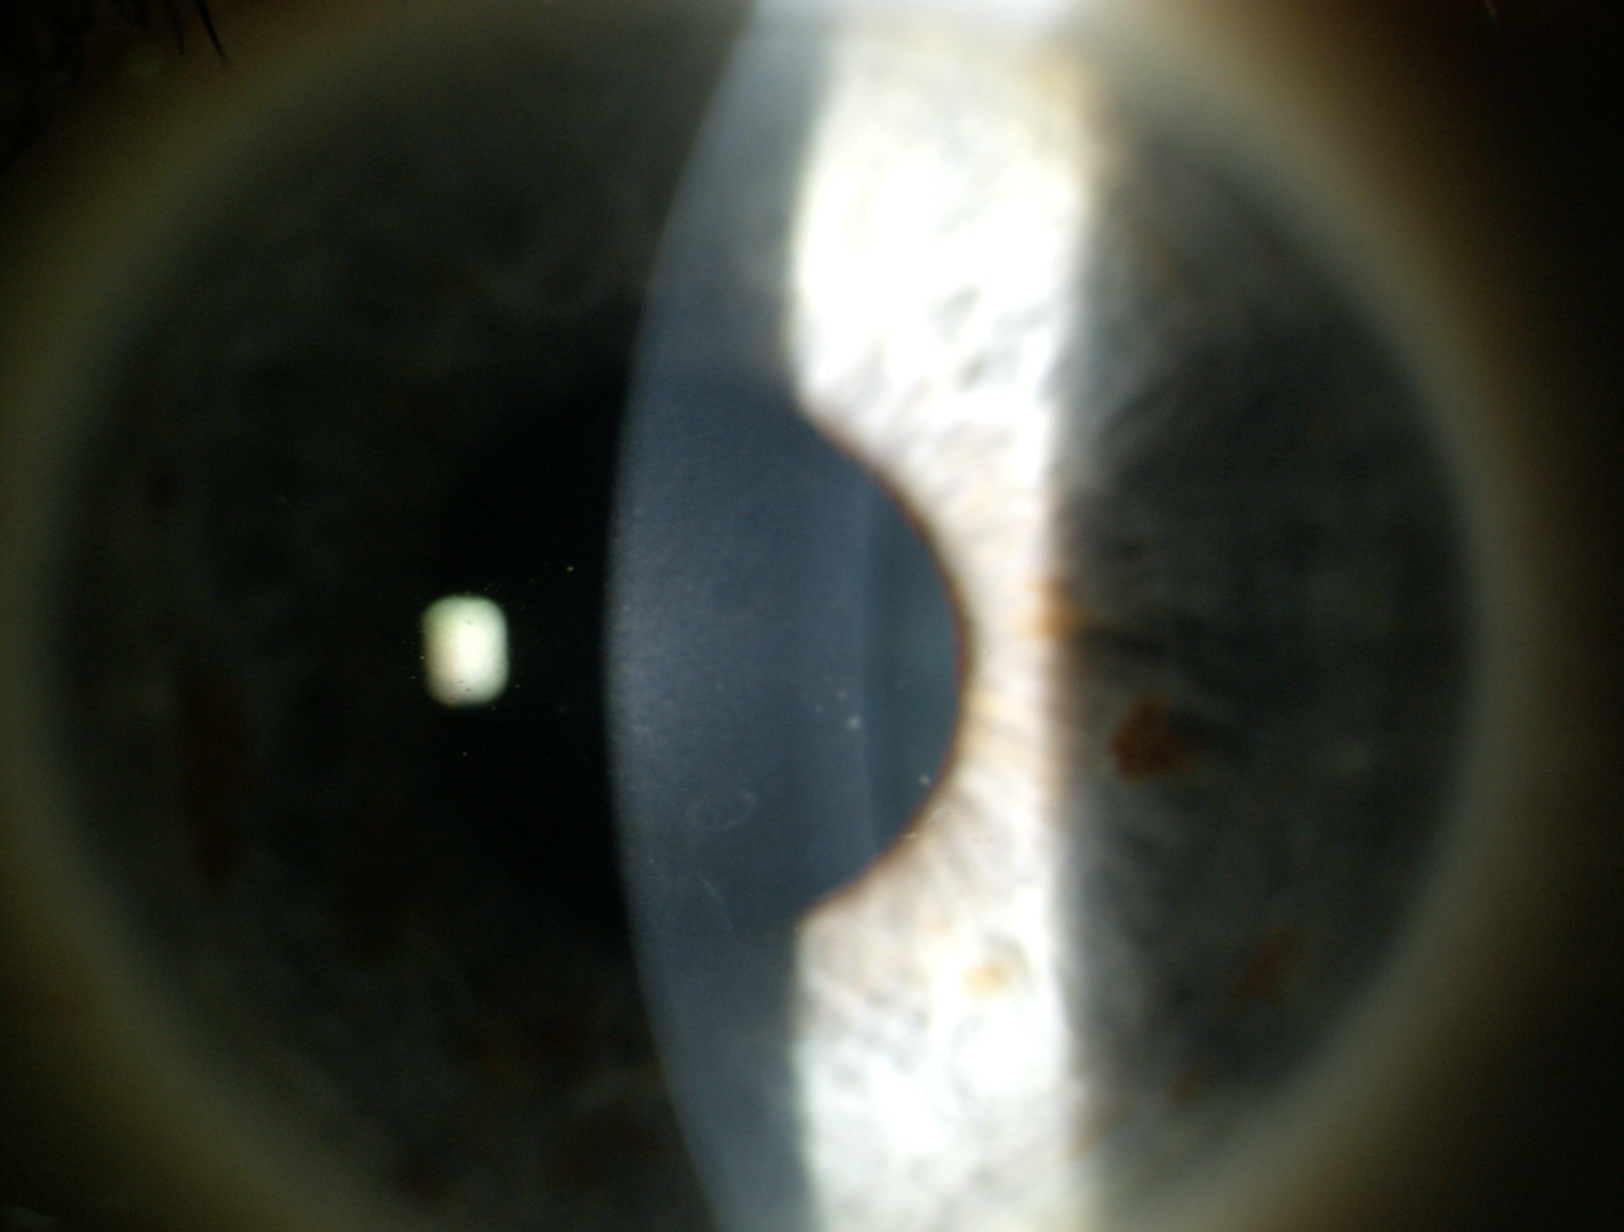

Paziente di 35 anni con pregressa storia di cheratoplastica lamellare per cheratocono e atrofia iridea. Il visus era di 1/10 con correzione ottica e di 5/10 con foro e correzione ottica

L’esame oculistico evidenzia un lembo corneale ben posizionato con lieve fibrosi dello strato profondo in sede centro paracentrale e una pupilla in midriasi fissa con atrofia dell’iride (vedi foto 1). Prima di pensare ad una correzione chirurgica si decide di provare una lente a contatto a disegno irideo con correzione contestuale del difetto refrattivo per verificare la possibilità di ottenere un visus soddisfacente per il paziente (vedi foto 2).

Il visus raggiunto con la lente a contatto è di 6/10. Il paziente è soddisfatto sia dal punto di vista quantitativo che qualitativo e la lente a contatto è ben tollerata da mesi. In accordo col paziente si decide di proseguire con l’utilizzo della lente a contatto a disegno irideo e di tener controllata la situazione oculistica con visite periodiche.